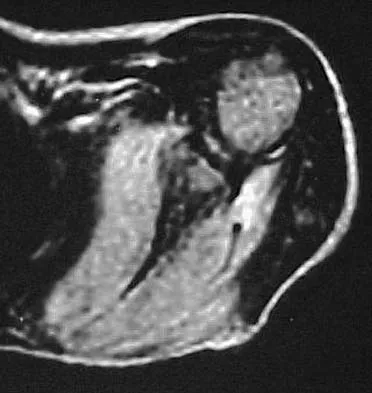

Question 49

Figure 50 shows the MRI scan of a 20-year-old female college soccer player with knee pain. What is the most likely diagnosis?

Anatomy Board Review 2002: High-Yield MCQs (Set 4) - Figure 13

Explanation

The MRI scan shows an acute complete tear of the posterior cruciate ligament. No evidence is seen of a quadriceps tendon rupture, a tibia fracture, or a bone contusion. Beaty JH (ed): Orthopaedic Knowledge Update 6. Rosemont, IL, American Academy of Orthopaedic Surgeons, 1999, pp 533-557.